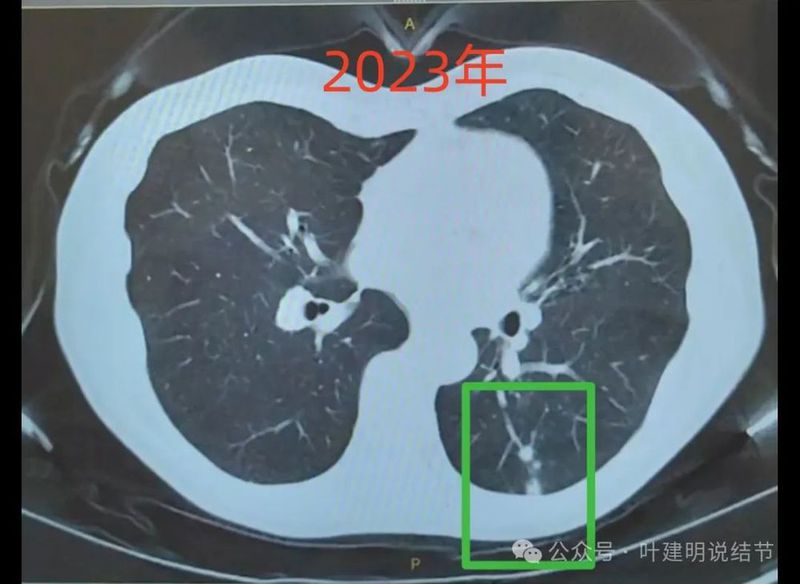

2023年时左下叶病灶,散在,多中心,密度较高,贴着胸膜无明显牵拉。

绿色的是今年与去年基本没有明显变化的,而且多中心,斑点状,考虑是慢性炎可能性大;粉色的右侧的是磨玻璃密度,对比持续存在,轮廓与边界清楚,这个要考虑肿瘤范畴的,但以原位癌可能性较大,目前风险仍不高,能随访;红色的是主病灶,今年发现的,但去年的影像上没有,新发现的这种形态上,首先要考虑是炎性的,至少不能先马上考虑恶性。我的想法是先抗炎治疗10-12天,然后过4周左右复查平扫CT,如果有吸收好转,当然证明是炎性的。如果没有好转,并有进展再来考虑穿刺活检也一样的。穿刺若非肿瘤性,不存在导致转移播散之说,如果穿刺明确是恶性,则接下去就要考虑手术的(如果是原发肺癌),所以也不至于就会因穿刺导致转移而影响预后。当然若抗炎无好转,并高度怀疑恶性,位置在边上,单孔局部楔形切了也是可以的,标本量更够,兼具诊断与治疗双重作用。个人想法考虑良性可能性大,建议先抗炎后复查再决定。意见供参考!